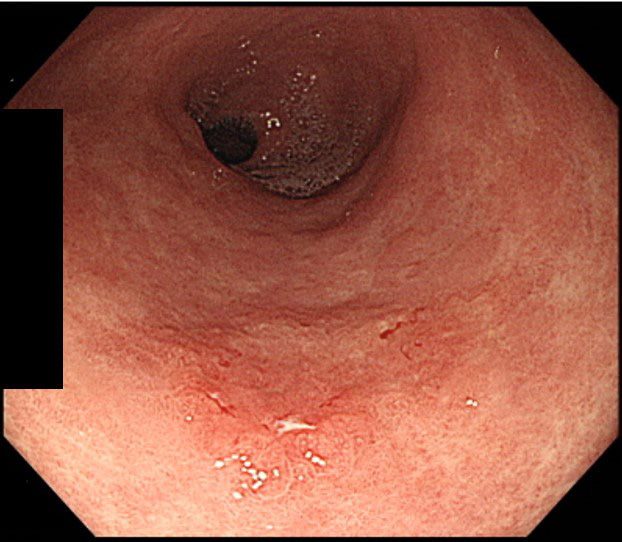

萎縮性胃炎

慢性的な胃粘膜の炎症によって、萎縮が起こっている状態です。原因のほとんどはピロリ菌感染とされており、胃がんリスクが高い状態です。胃がその機能を十分に果たせなくなるため、胸やけ、胃もたれ、腹満感、食欲不振などの症状を起こします。胃カメラ検査で粘膜の状態を直接確認し、組織採取による確定診断やピロリ菌感染検査を行います。ピロリ菌感染陽性だった場合には除菌治療を行います。